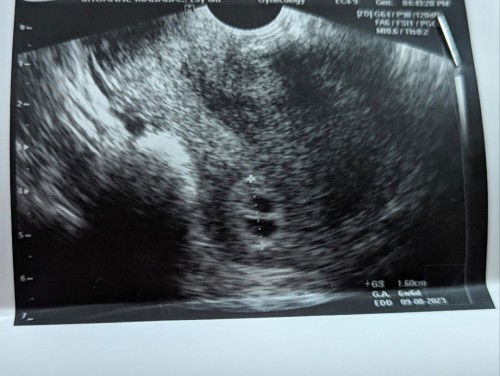

PREGNANT OF TWINS?

Got my first ultrasound. Too early to say pero may chance po ba na twins ito? Para daw kasing dalawa yung gestational sac. Sino po naka-experience ng ganito. 6 weeks pregnant and need bumalik at magpa-ultrasound after 4 weeks #pleasehelp #advicepls #twins